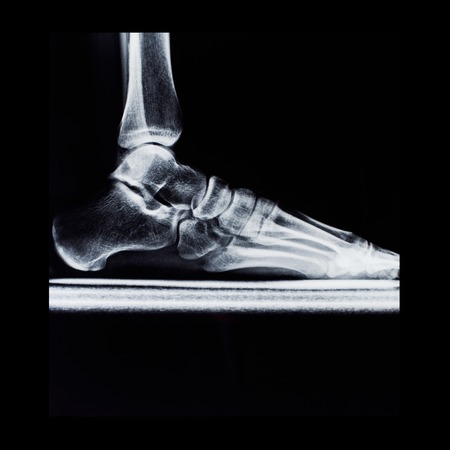

Detail of the x-ray of a human foot in black and white

x-ray image of human foot

x-ray of foot of diabetic showing calcified artery

Fluorography of foot with deformation in black frame